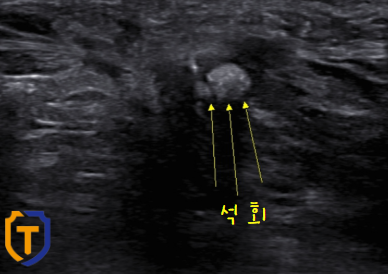

- 엑스레이(xr)

- 정밀 초음파

이 2가지의 검사로 석회가 있어서 손목의 통증이 일어난걸로 확인이 된답니다.